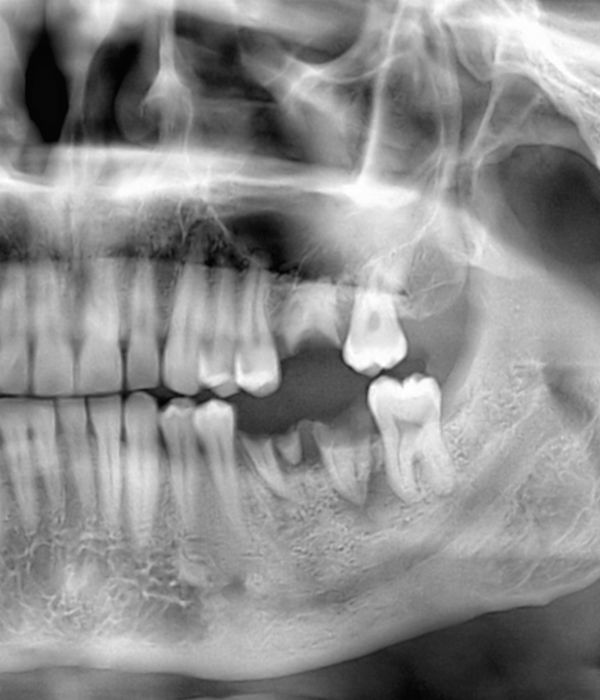

Extractions

If you require an extraction, our surgeons will use gentle techniques to remove your damaged tooth and preserve the surrounding bone structure. Our sedation options can also keep you comfortable and relaxed during the procedure. Often, we can combine extractions with same-day dental implants.